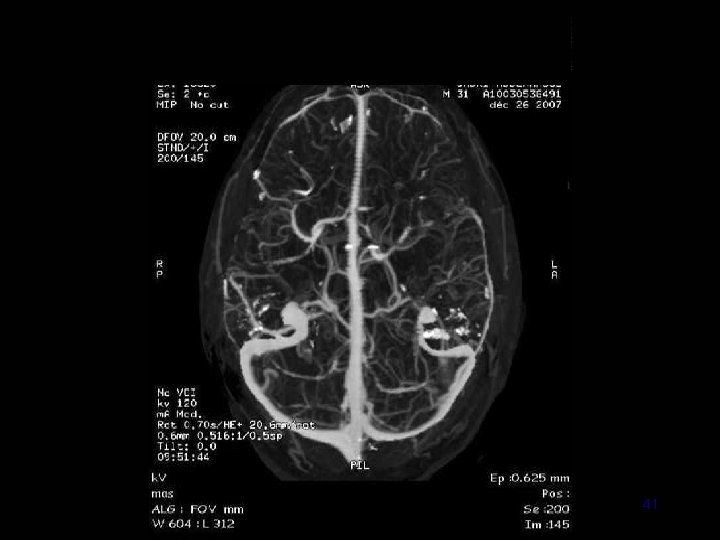

40

41

IRM • Diagnostic: – Sagittales T 1 en SE +++ – Coronales T 2 ou Flair – Axiales T 2 EG ++ +/- Coronales T 1 sans et avec Gado • Extension (et suivi) : ARM veineuse – – Contraste de phase 3 D PC Temps de vol 2 D TOF veineux Acquisition volumique +Gd ARM dynamique 42

Angio IRM (ARM) 3 D PC 2 D TOF veineux 3 D Gd+ 58

• 2 D TOF veineux – Rapide – C– Faux + • 3 D Gd + – Rapide ++ – Sinus et veines corticales 60